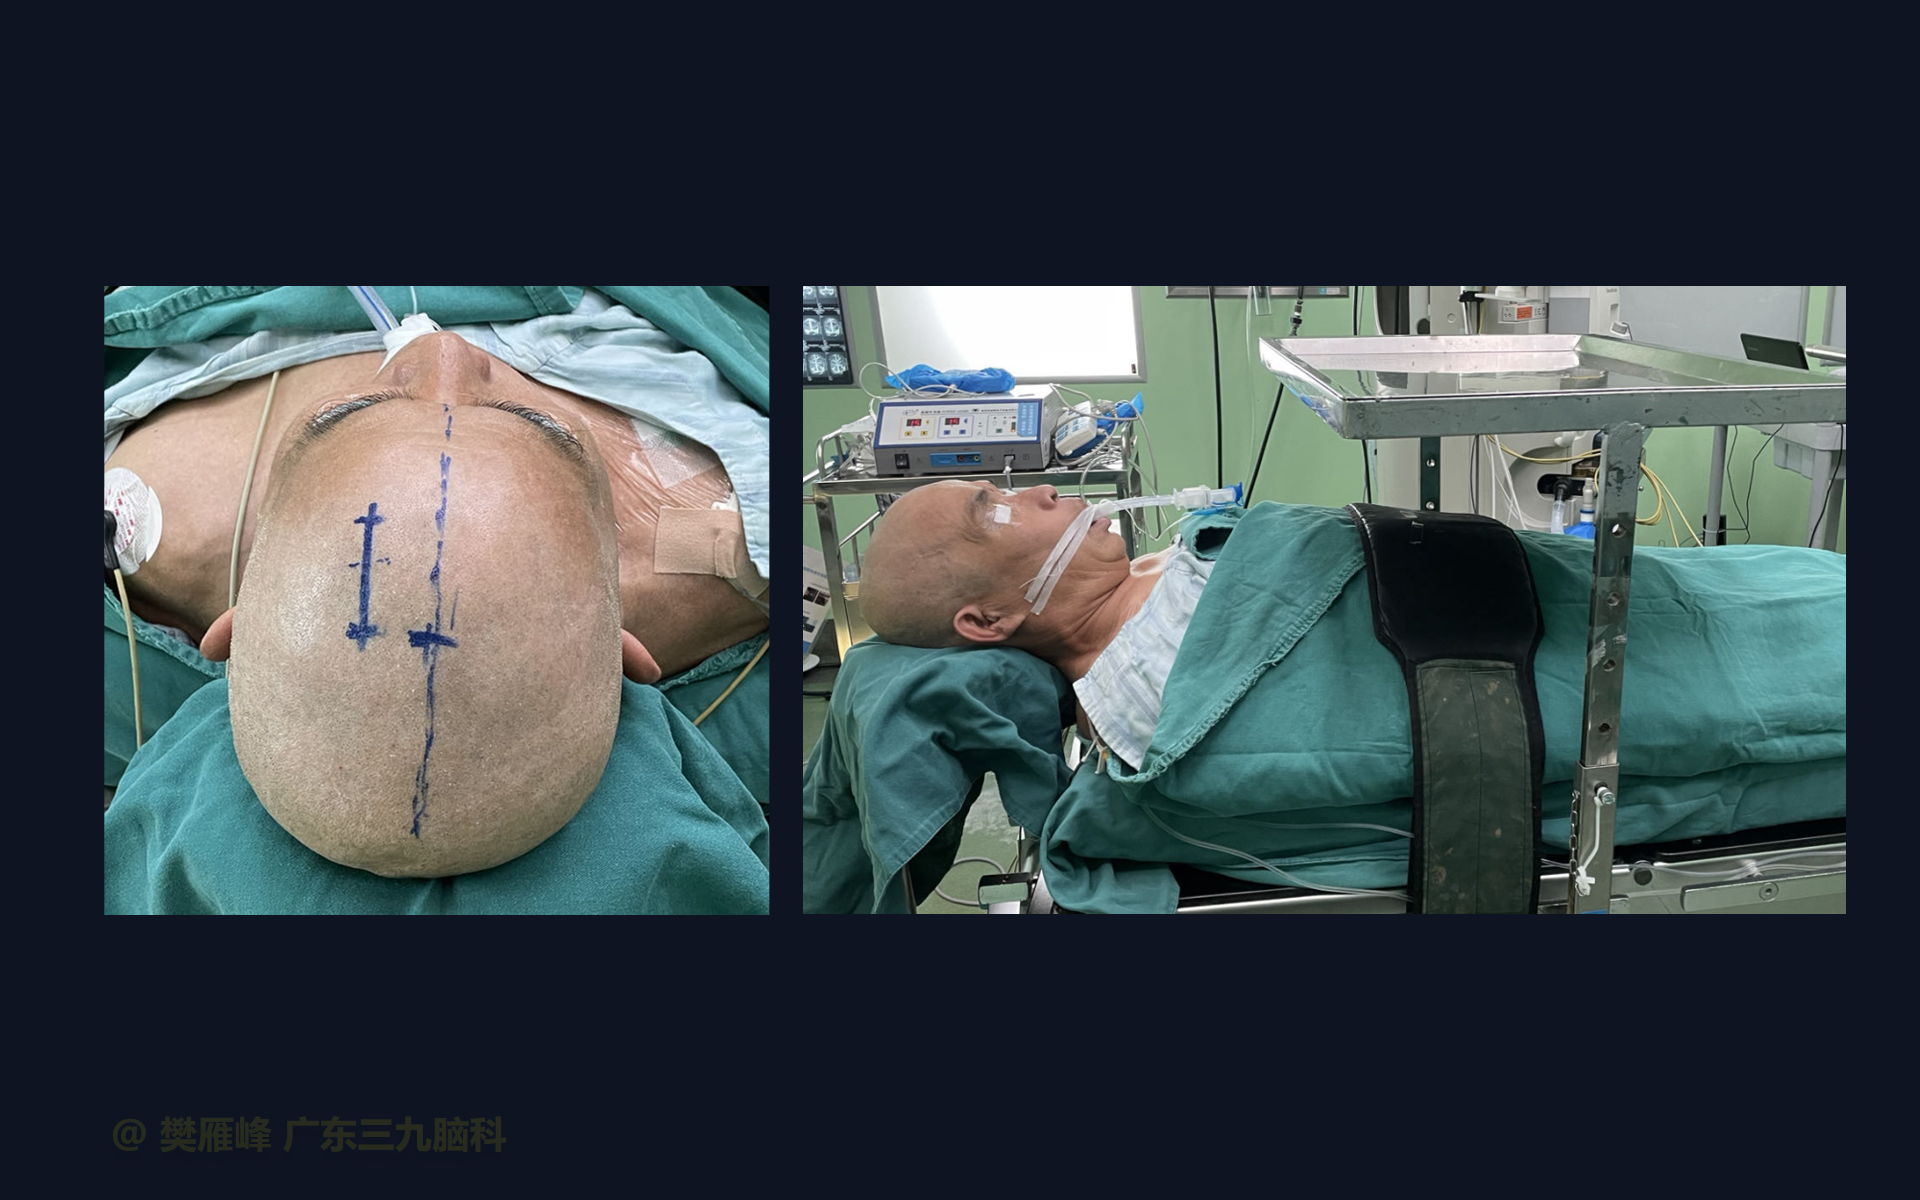

在这个二维手术视频中,展示了2例神经内镜下三脑室底造瘘+活检治疗三脑室后部肿瘤的方法。患者均为三脑室后部病变导致的梗阻性脑积水,病理结果1例为生殖细胞瘤,1例为淋巴瘤,在经过术后的放化疗病情均得到控制,生活质量满意。我们展示了安全的病变活检和第三脑室造瘘的技术要点,以最大限度减少术后继发脑积水和早期并发症。